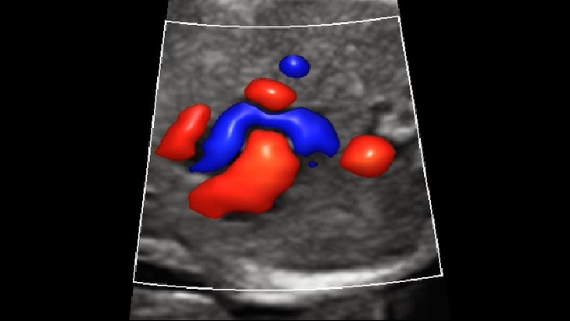

ImĂĄgenes clĂnicas